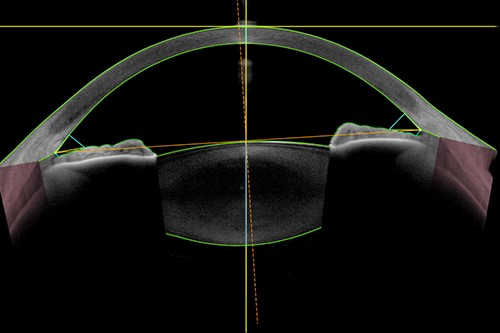

Anterior chamber metrics based on the automatic detection of the scleral spurs

- The Metrics App to automatically detect the scleral spur and calculate many biometric parameters to improve workflow and precise anterior chamber parameters